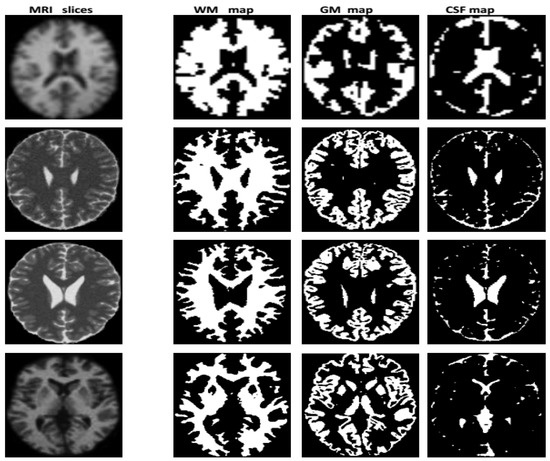

The result obtained from the execution of the modeling process to the image k ∈ {1..P} is a series of three fuzzy maps corresponding to the tissue T∈ {CSF, GM, WM} estimated from the image k. Figure 3 illustrates the results of some slices which are chosen because of their tissue particularities. In this figure and in each map, the WM, GM and CSF tissues are expressed by the zones with white color. These fuzzy maps are related to three distributions of possibility π i T ( i = 1 .. N ¯ voxels ), where the value π i T ( v ) is the membership of voxel v to tissue T computed from image k. Two sets of fuzzy maps are obtained for MRI and PET images: {WMMRI, GMMRI, CSFMRI}, {WMPETI, GMPET, CSFPET}. These maps are used in the next step to obtain fusion maps.